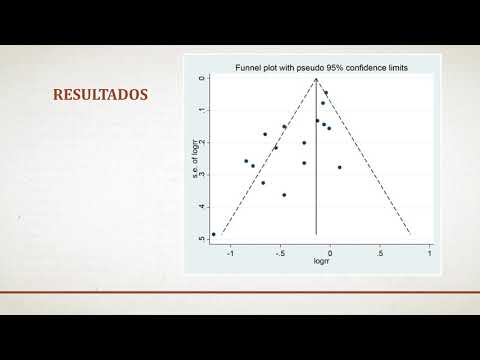

Eficacia y seguridad de los stent liberadores de droga optimizados por biocompatibilidad vs. stent metálicos con solo un mes de doble antiagregación. Dra. Florencia Cichello. Residencia de Cardiología. Hospital C. Argerich. Buenos Aires